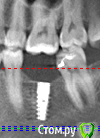

Елена83 Опубликовано 31 марта, 2016 Поделиться Опубликовано 31 марта, 2016 Здравствуйте!Мне устанавливают имплант на нижнюю 6ку. Сняли слепки для изготовления коронки, доктор сказал, что верхний зуб будет подпиливать. Только теперь начинаю беспокоиться, что это значит??Этот зуб нужно будет депульпировать? Нельзя ли нижнюю коронку изготовить более низкой, а верхний зуб оставить в прежнем выдвинутом состоянии?? Ссылка на комментарий

___49___ Опубликовано 31 марта, 2016 Поделиться Опубликовано 31 марта, 2016 (изменено) Депульпировать ...зачем ? не вижу в этом смысла. А чтобы ответить на ваш последний вопрос более полно - боюсь одиночного дентального снимка будет мало . Изменено 31 марта, 2016 пользователем ___49___ Ссылка на комментарий

anvladd Опубликовано 31 марта, 2016 Поделиться Опубликовано 31 марта, 2016 Здравствуйте!Мне устанавливают имплант на нижнюю 6ку. Сняли слепки для изготовления коронки, доктор сказал, что верхний зуб будет подпиливать. Только теперь начинаю беспокоиться, что это значит??Этот зуб нужно будет депульпировать? Нельзя ли нижнюю коронку изготовить более низкой, а верхний зуб оставить в прежнем выдвинутом состоянии??а не пломба ли на верхнем зубе? Тогда вообще не парьтесь. Ссылка на комментарий